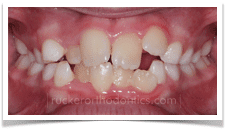

Crowding: This is one of the most common reasons for early orthodontic treatment. Simply put, adult sized teeth are trying to fit in child sized jaws. This mismatch creates an obvious dental situation in which arch development, or widening, through orthodontic treatment is required to create space for permanent tooth eruption. Early correction can also prevent more serious complications such as tooth impactions.